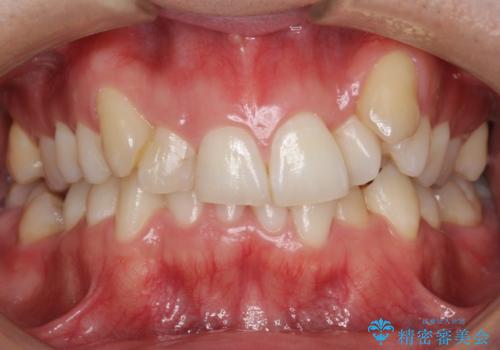

ワイヤーによる全体的ながたつきの矯正治療